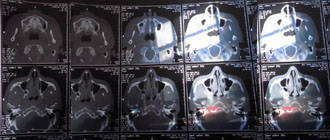

CT圖像故障分析與判斷

CT圖像異常的故障比較多見,表現(xiàn)的形態(tài)也各不相同,如雪花點、螺紋影、同心圓、條紋影等,無論是機械故障、電器故障、還是軟件故障,都可能反映在圖像上表現(xiàn)為異常偽影。

CT偽影分析

CT圖像上的偽影是指在成像過程中產(chǎn)生與被掃描組織結(jié)構(gòu)無關(guān)的異常影像。分析和判斷偽影的形成原因,認識偽影的各種特征。才能迅速排除問題,最大限度的減少因偽影。